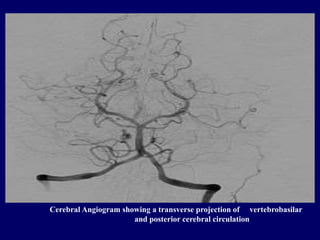

5. Cerebral Angiography

-Invasive and involves the

injection of radiopaque dye into

blood vessels with subsequent

radiography

Cerebral Angiogram showing a transverse projection of vertebrobasilar

and posterior cerebral circulation